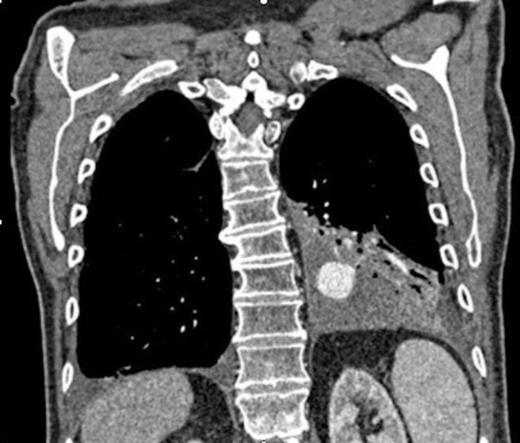

Left pulmonary artery digital subtraction angiography image demonstrating filling of left lower lobe aneurysm (arrow)

Digital subtraction angiography post deployment of the AVP 4 device in the PA branch feeding the aneurysm (arrow). No residual or collateral filling seen